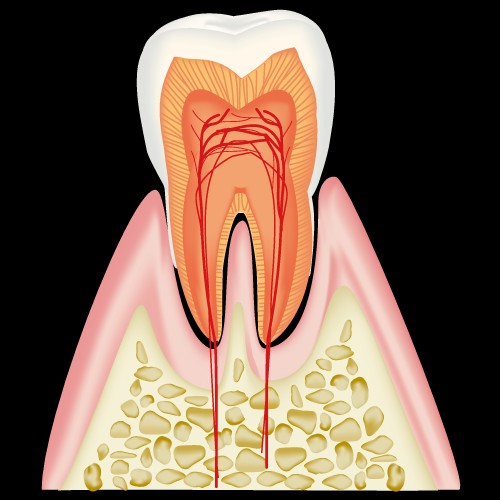

歯は三層に別れていて

- エナメル質

- 象牙質

- 歯髄

と呼ばれ、どこまで到達したか、が分類の基準となります。

C3:歯髄まで進行した虫歯